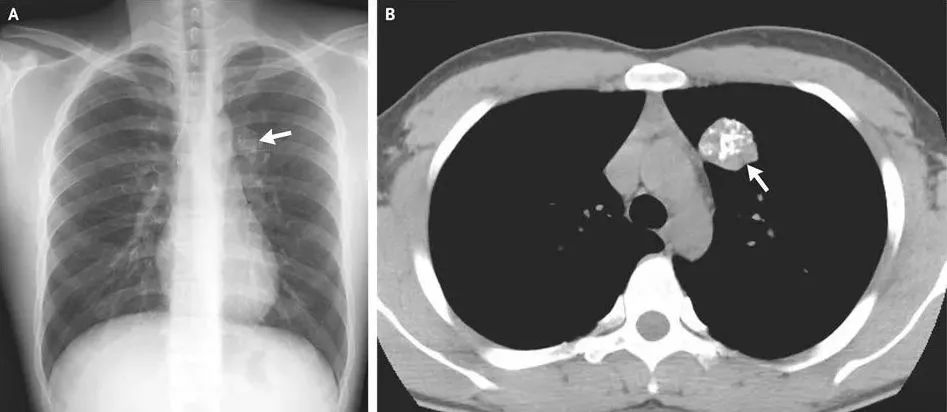

▌肺部钙化

一般来说,肺部的单个或少量钙化灶多为陈旧性病变遗留,通常无需特殊治疗,定期复查观察即可。但如果钙化灶较大或数量较多,伴有其他异常表现,如咳嗽、咳痰、咯血、胸痛等,则需要进一步检查。